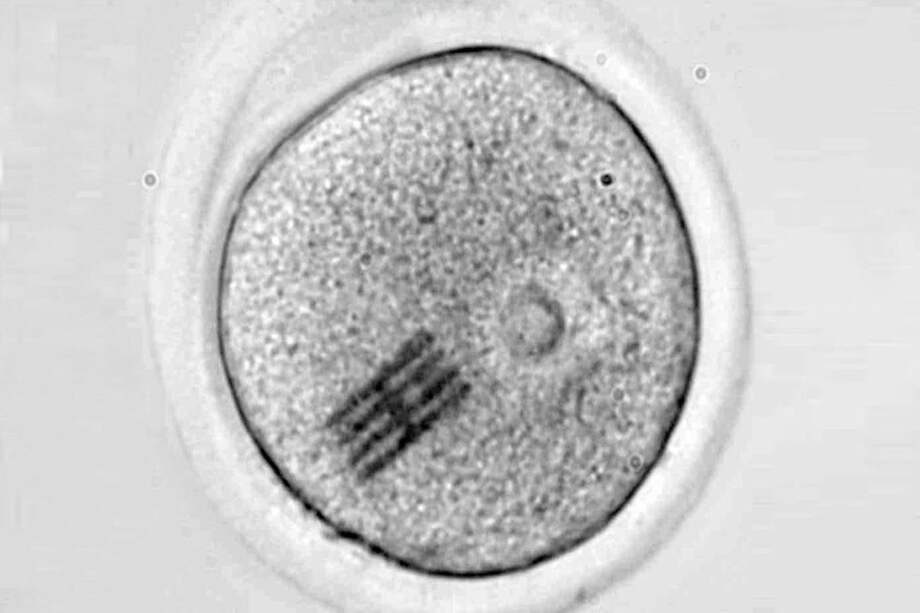

Investigadores del Instituto de Microelectrónica de Barcelona (IMB-CNM) del CSIC y la Universidad de Bath (Reino Unido) han fabricado e introducido chips dentro de células vivas para detectar los cambios mecánicos que se producen en las primeras etapas del desarrollo embrionario. Los detalles los publican esta semana en la revista Nature Materials.

El chip funciona como sensor mecánico y es extremadamente minúsculo: mide apenas 22 por 10,5 micrometros, con 25 nanometros de grosor. Esto significa que tiene una longitud tres veces más pequeña que el diámetro de un cabello humano, y un espesor tres veces menor que el de un virus como el SARS-CoV-2.

Los dispositivos se han fabricado en la sala blanca del IMB-CNM bajo la supervisión del científico José Antonio Plaza. Luego, en un laboratorio de la Universidad de Bath, otro equipo dirigido por Anthony C. F. Perry ha inyectado el chip junto con un espermatozoide en el interior de un óvulo de ratón para analizar las etapas tempranas de la fertilización. Este proceso inicial ocurre de forma similar en los humanos.

Con el dispositivo dentro, han podido medir las fuerzas que reorganizan el interior del óvulo, es decir, su citoplasma, desde que se introduce el espermatozoide hasta que se divide en dos células.

“Haciendo un símil con el baile, el embrión realiza una coreografía de movimientos durante su desarrollo y hemos visto que no sólo el movimiento es importante sino también la intensidad del mismo”, comenta Plaza, “y a través de microscopia, podemos ver cómo el chip se dobla en el interior de la célula”.

“Dado que hemos modelizado y conocemos perfectamente qué fuerza hay que aplicar para que se doble el chip de una determinada manera –añade–, visualizando la curvatura podemos inferir qué fuerzas mecánicas se están dando en el interior celular”.